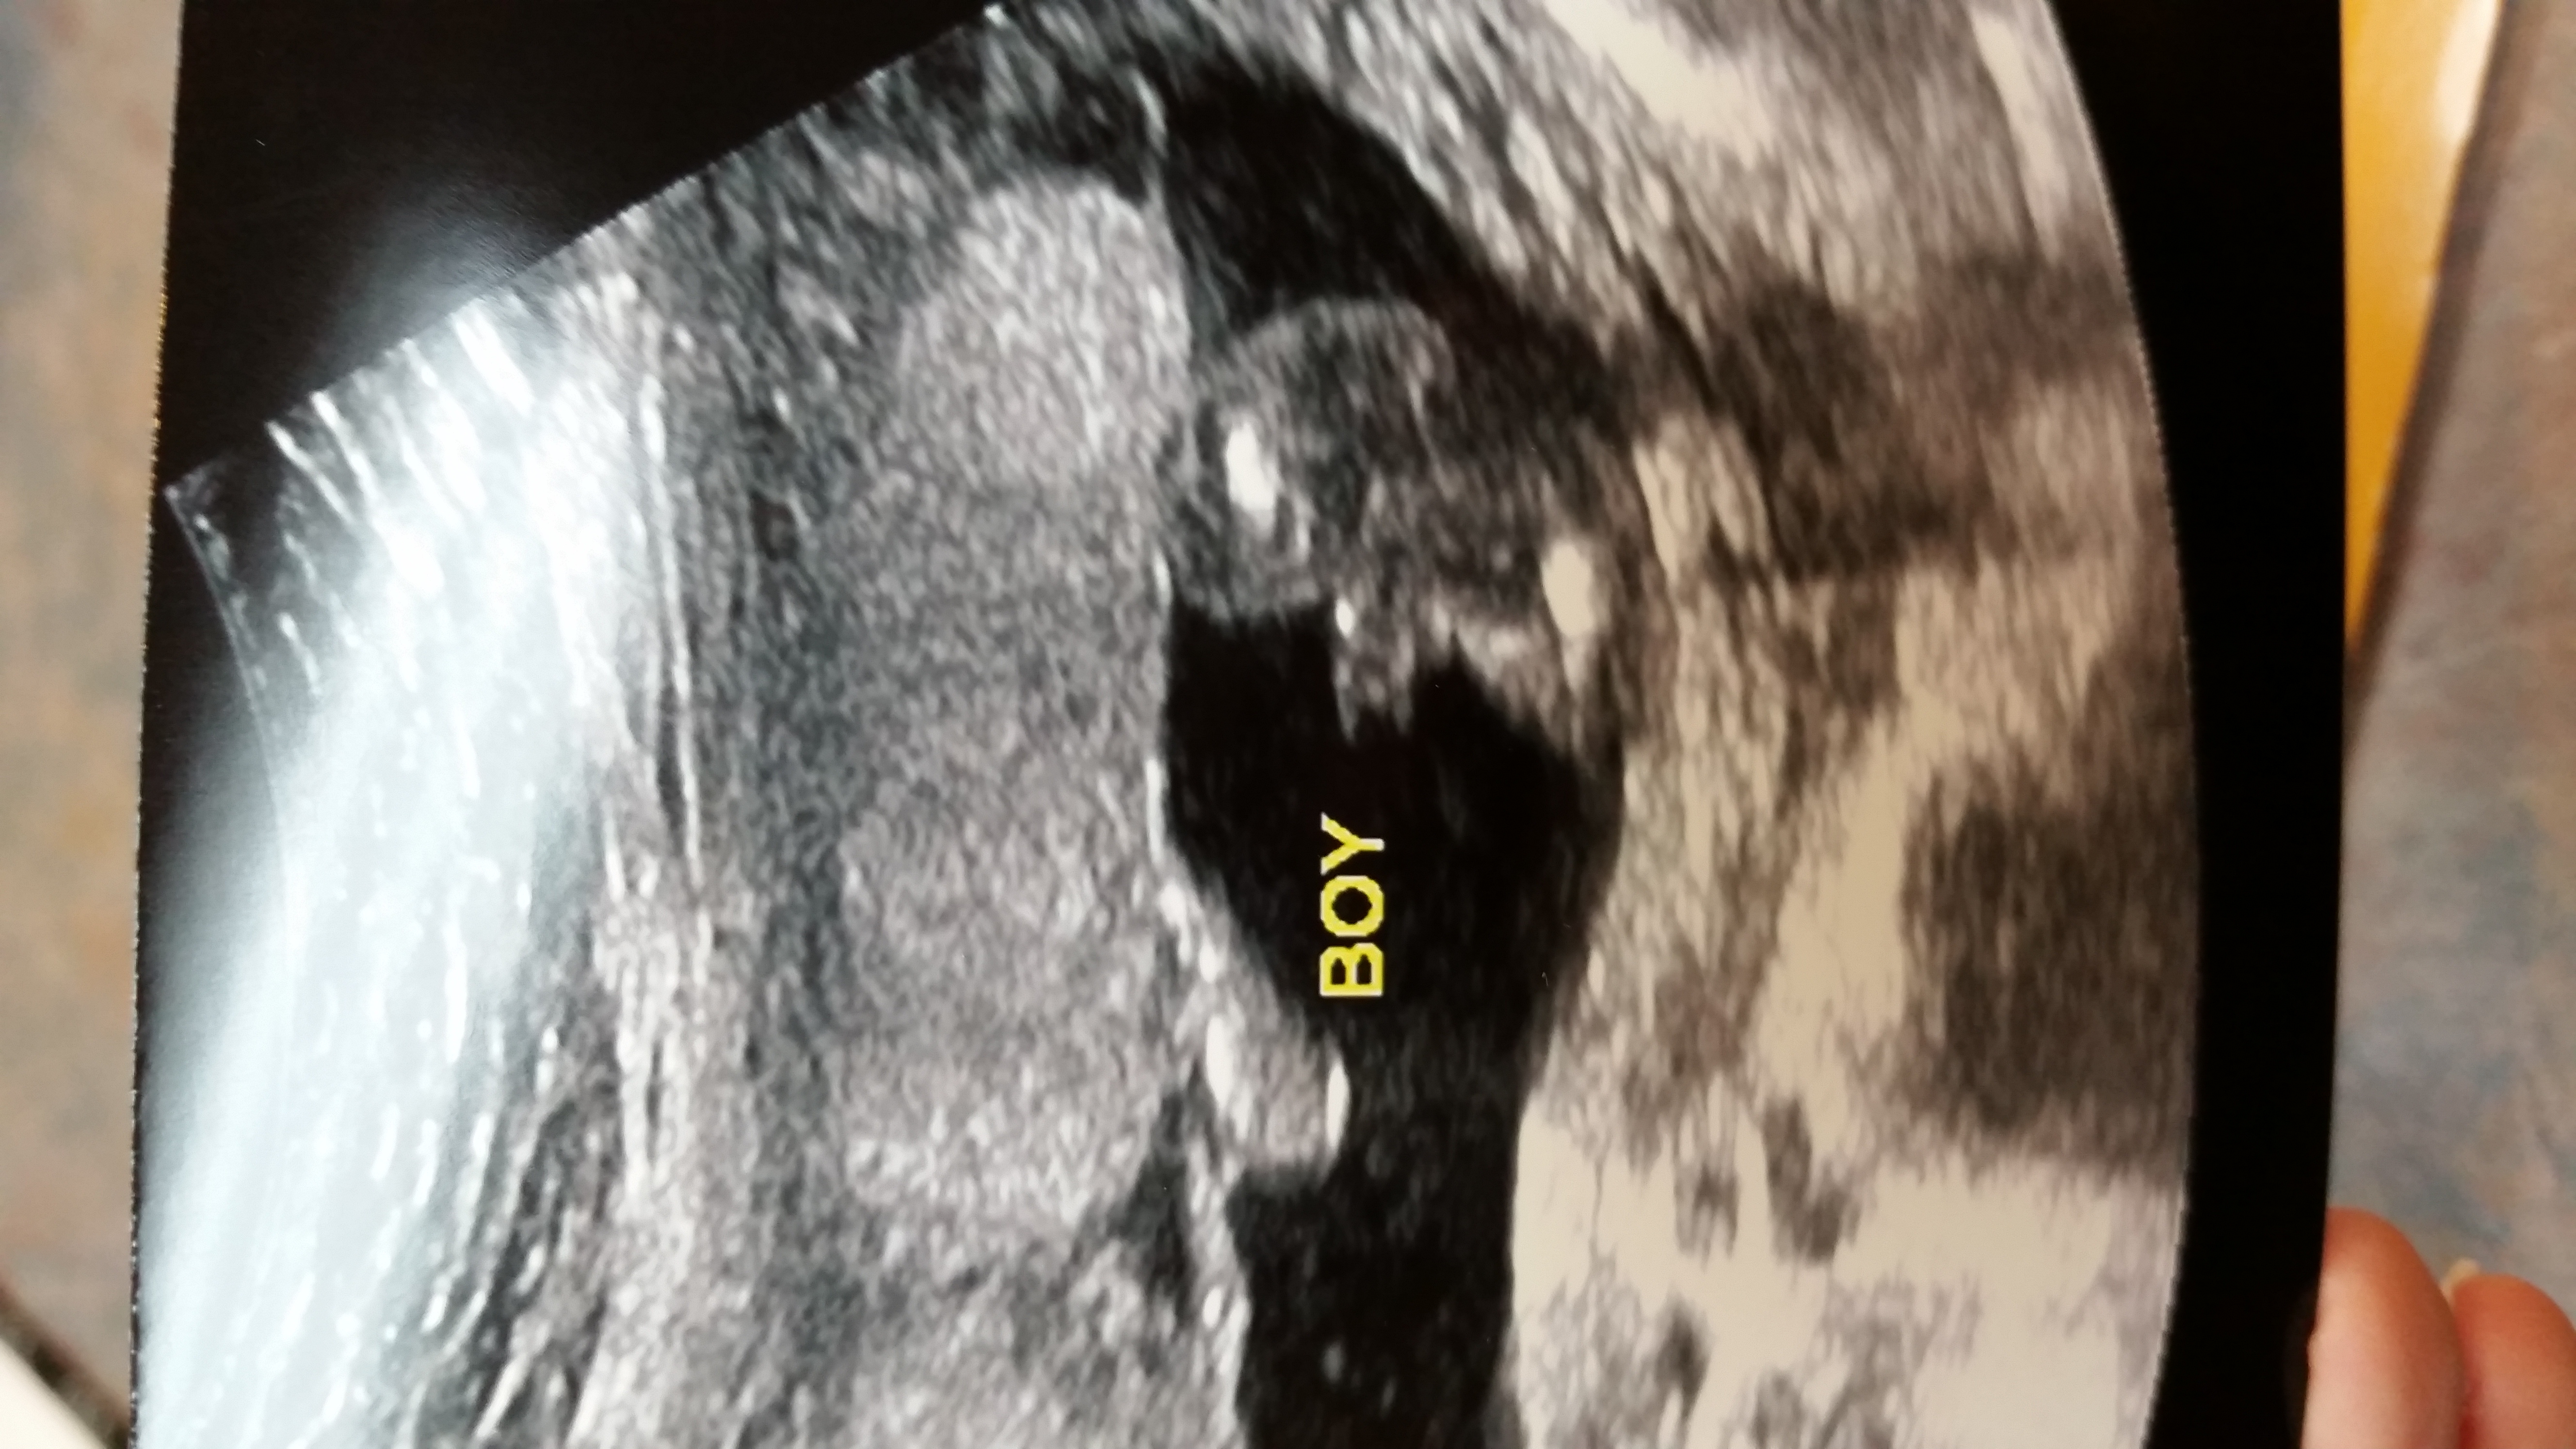

Attachment 2048418 week ultrasound

All boy

Definitely a boy

Yes I was told it was a girl a week and half ago and now they're saying boy. First guess was grin the Dr and this one was from a tech

boy